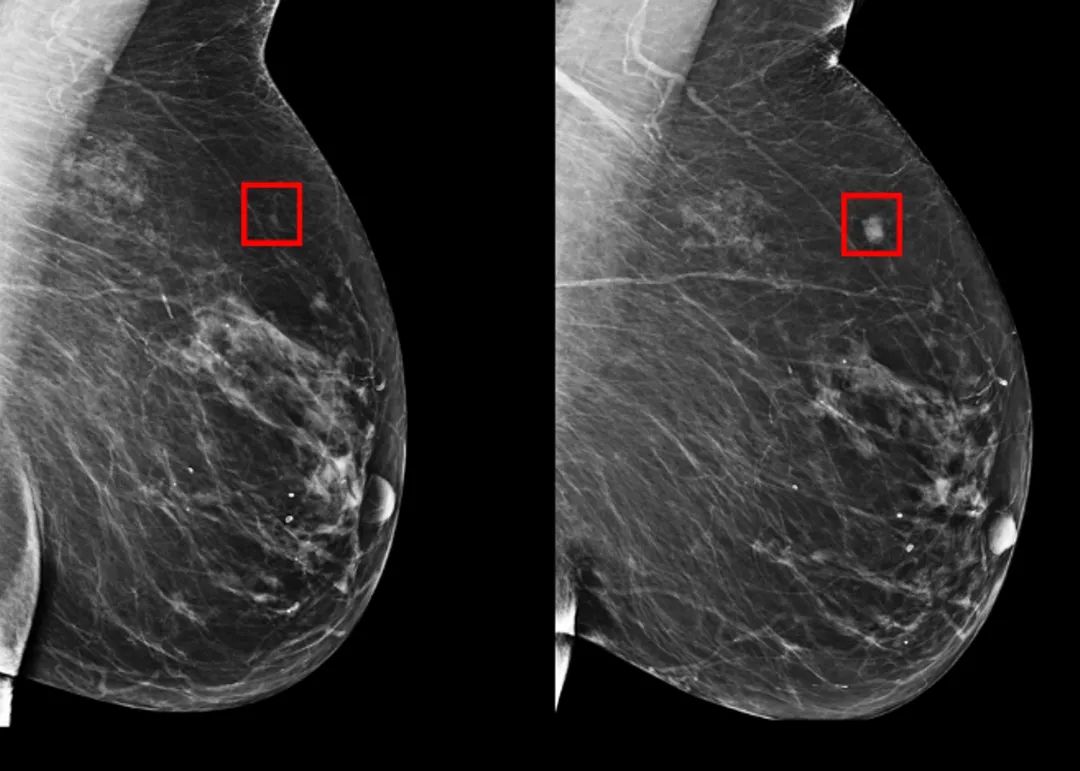

La inteligencia artificial predijo el 31% de los casos de pacientes de alto riesgo